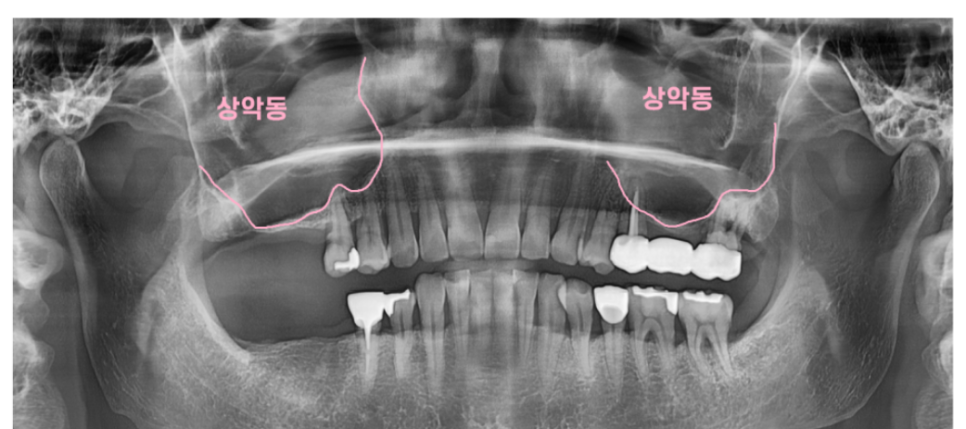

먼저 윗턱 임플란트 수술 시

언급되는 상악동거상술

상악에 하는 뼈이식이라 생각하시면 됩니다.

뼈만 이식하는 것이 아닌

상악동을 들어올리면서 동시에 뼈까지 이식하기에

상악동거상술이라고 부릅니다.

하악 어금니 임플란트 수술 시에는 하치조신경을 조심해야한다면

상악 수술 시에는 이 상악동을 조심하여야하는데요.

그 이유가 코피가 나는 이유와도 연결되어있습니다.